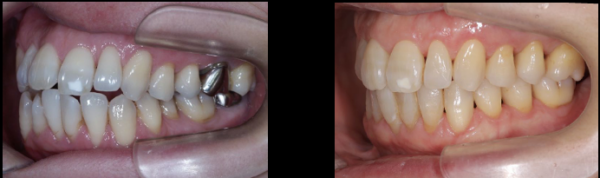

そして、治療終了後20年の状態です。

患者さまは還暦を迎えられましたが、お口の中は非常に健康で若々しい状態を保っておられます。

(左:治療前 右:治療終了後20年経過時)